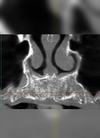

Le cliché 3D pré-opératoire révèle une cloison (ou refend) au sein du sinus maxillaire droit d’une patiente de 67 ans.

Deux fenêtres sont réalisées, l’une en arrière et l’autre en avant du refend, et une membrane d’origine porcine est placée et suturée dans chaque cavité avant le comblement osseux.

Le cliché 3D post-opératoire montre les deux implants vissés de part et d’autre du refend et dans la masse des deux comblements osseux réalisés indépendamment .